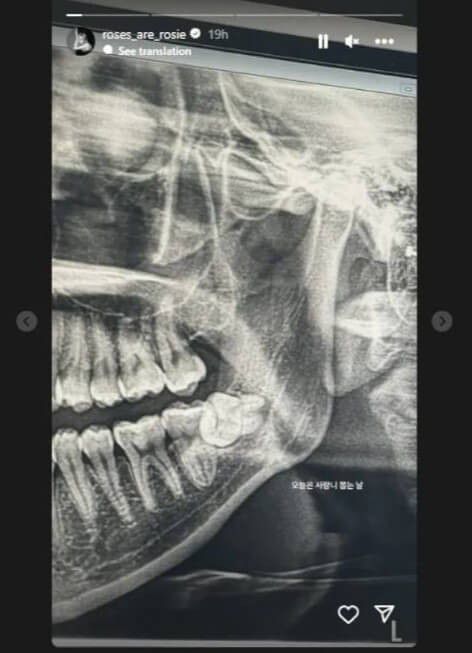

Rose BLACKPINK belum lama ini mengunggah kondisi kesehatan giginya di media sosial.

Wanita dengan nama asli Park Chaeyoung memperlihatkan hasil rontgen giginya yang bermasalah. Dari unggahan tersebut, tampak kondisi gigi bungsu Rose tumbuh dalam kondisi miring.

Ternyata, kondisi ini disebut dengan istilah impacted wisdom teeth atau gigi bungsu tumbuh miring. Penyanyi lagu On The Ground itu memiliki posisi gigi bungsu yang menyundul gigi lainnya.

"Hari ini adalah hari di mana aku cabut gig bungsuku," tulis Rose dalam keterangan unggahannya, Selasa (24/10).

Usai mengunggah foto rontgen, ia kemudian mengunggah foto dirinya yang sedang mengkompres pipinya karena mengalami pembengkakan.